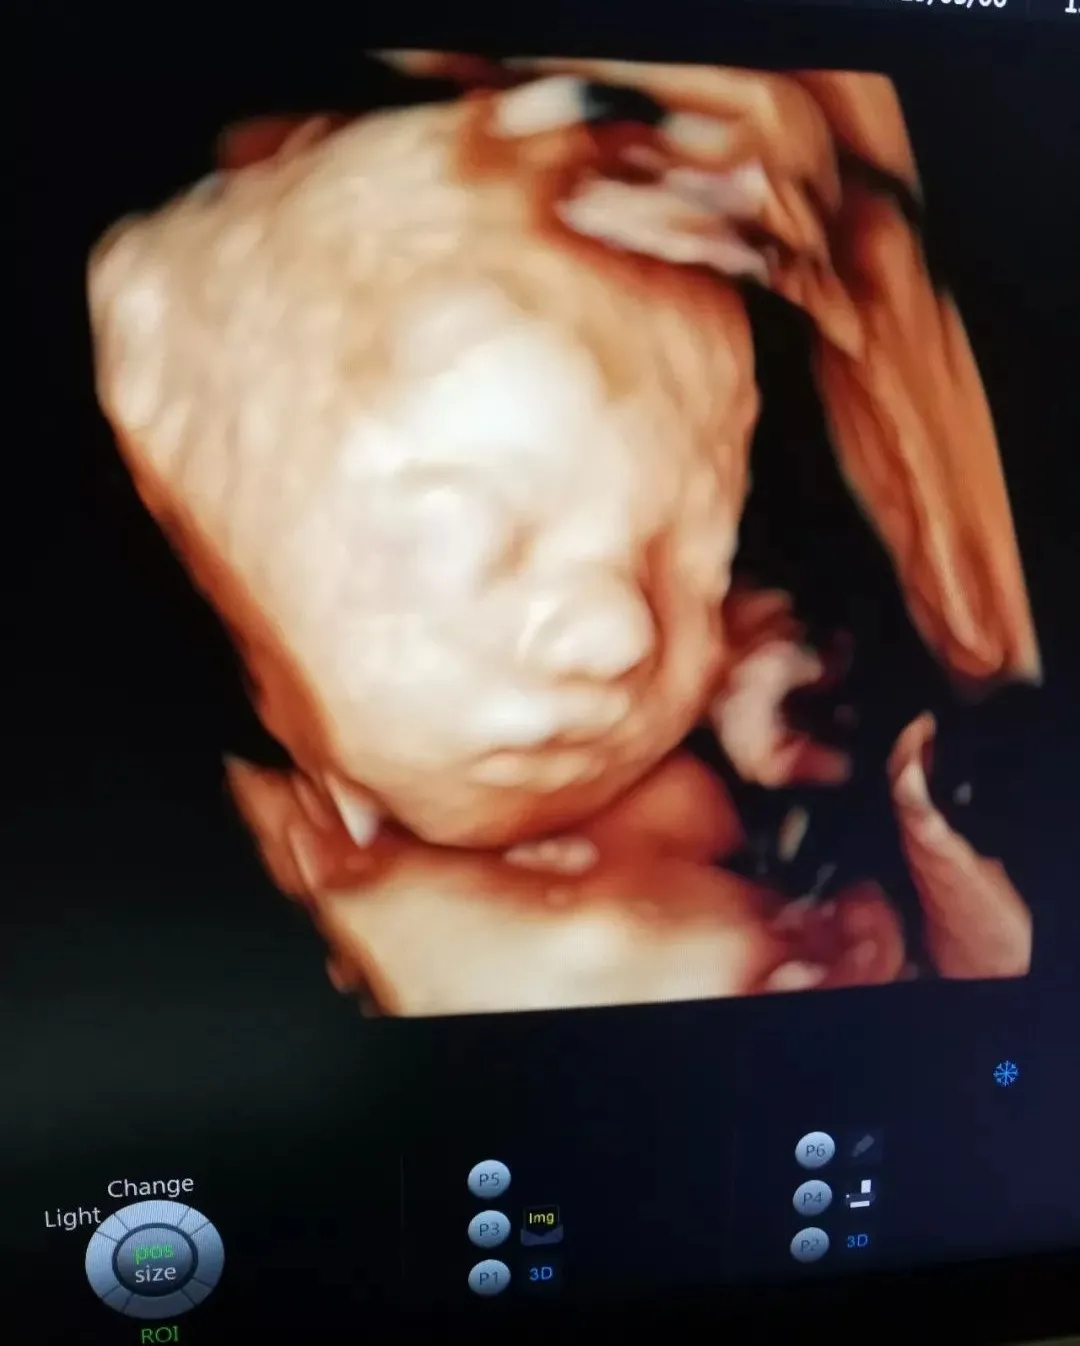

与胎宝紧密相连280天里,一次次胎动是你们之间独特的交流方式,而这时,我们更加好奇胎宝每天都在妈妈肚子里干什么呢?看看这些四维彩超抓拍的胎宝的小模样吧!以下为胎宝的自白时间哦~!

但通过美琳达的四维彩超画面中

TA们的活泼好动,萌萌的表情

已经说明了一切